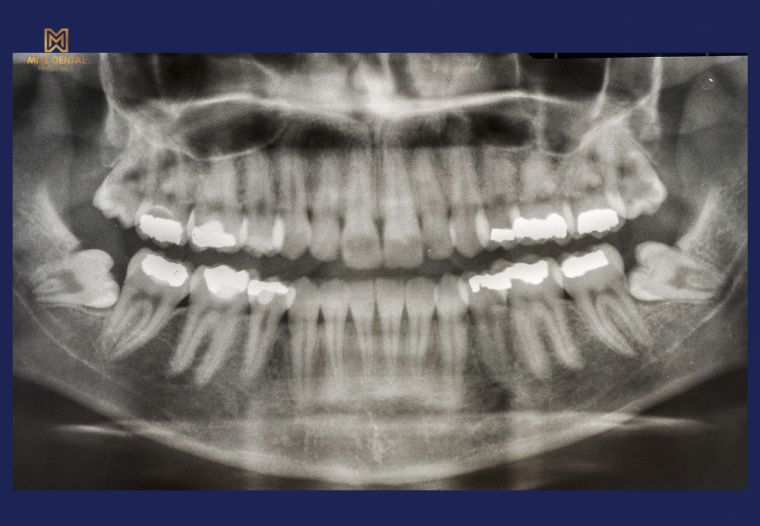

Thăm khám và chụp X-quang: Để xác định vị trí, hướng mọc của răng khôn.

Răng khôn là những chiếc răng hàm lớn mọc cuối cùng ở hai bên hàm trên và hàm dưới, thường xuất hiện trong độ tuổi từ 17 đến 25. Đây là những chiếc răng vĩnh viễn cuối cùng mọc lên và do sự tiến hóa của con người, xương hàm ngày càng nhỏ lại, khiến răng khôn không có đủ chỗ để mọc đúng cách. Vì vậy, răng khôn thường mọc lệch, mọc ngầm hoặc gây ra nhiều biến chứng nguy hiểm.

Một trong những vấn đề phổ biến nhất là răng khôn mọc lệch, nghiêng vào răng bên cạnh. Khi điều này xảy ra, răng khôn có thể gây chèn ép, làm hỏng cấu trúc răng bên cạnh, gây sâu răng hoặc tiêu xương.